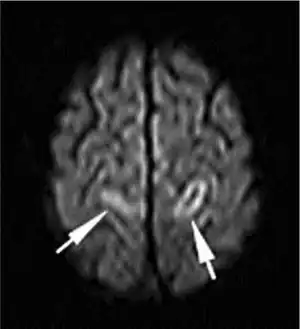

![]() | |

| A deep vein thrombosis in the right leg. There is striking redness and swelling. | |